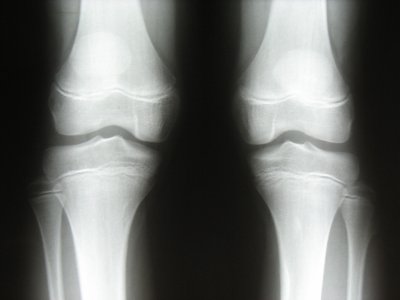

Gli accertamenti diagnostici eseguiti in ordine cronologico sono stati: un primo studio neurofisiologico che ha evidenziato mononeuropatia motoria peroneale sinistra; ecografia della testa fibulare sinistra che ha mostrato una irregolarit� della regione iuxtametafisaria prossimale della fibula con sollevamento del profilo corticale e radiografia in due proiezioni della regione di interesse che ha messo in evidenza una irregolare espansione del profilo osseo fibulare di circa 15 mm di dimensione, verosimilmente riferibile ad espostosi (Figura 1).

Figura 1. Alla radiografia si evidenzia, a livello della testa fibulare sinistra, una irregolare espansione del profilo osseo di circa 15 mm di dimensione, riferibile ad esostosi.